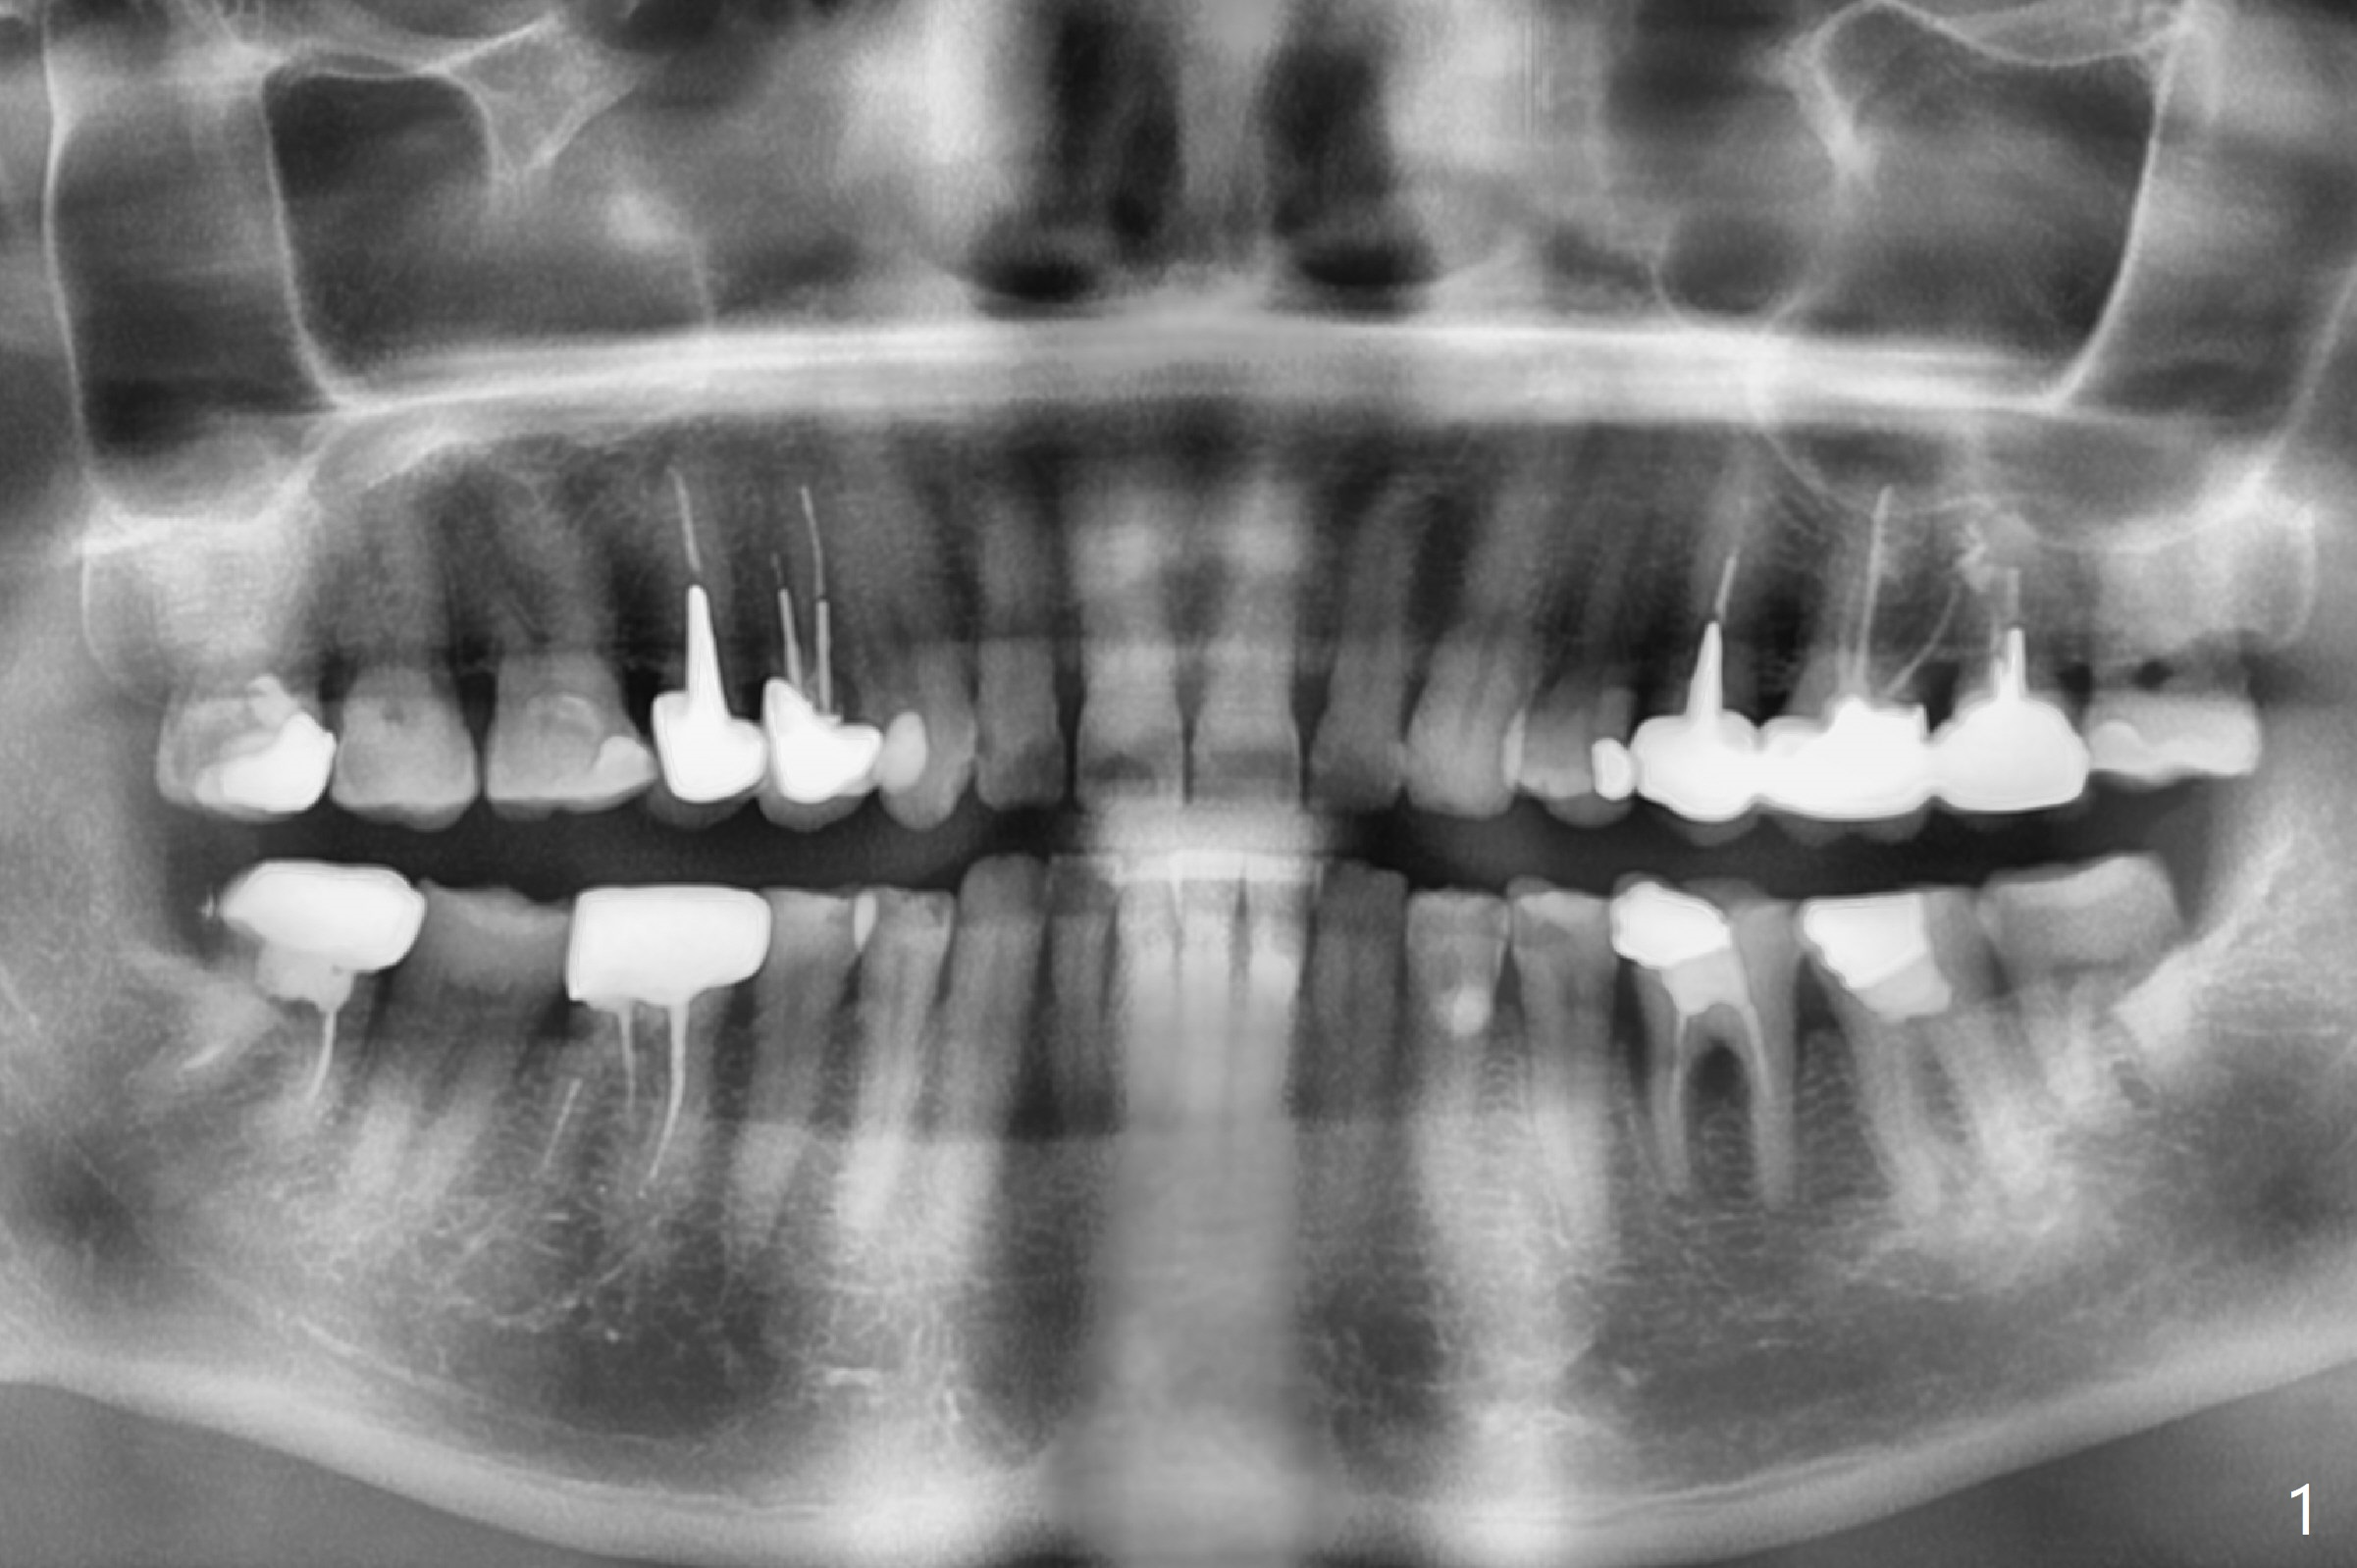

A 54-year-old man has several restoration with sign of bruxism (Fig.1). The tooth #19 has mesiodistal crack with furca radiolucency (Fig.2 *). To prevent abutment screw loosening associated with heavy mastication, a 6x17 mm tissue-level implant will be placed free hand due to the patient's tight schedule (blue, Fig.3,4,5). Pink: abutment; green: restoration which will be seated partially in the implant to reduce abutment loosening. To reduce possible neuropathy and have freedom to place implant deep, the implant length will be shorter, 14 mm, if the bone is dense. Take photos to show the crack line and buccal swelling. The patient returns for implant 4 months post extraction without bone graft in his home country with bone loss (Fig.6). In the presence of the accessory canal (Fig.7 *), a 5x10 mm implant is safe to be placed.